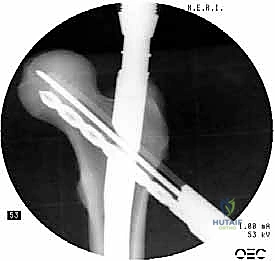

يتكون هذا النظام الجراحي من:

1. المسمار النخاعي الرئيسي (Intramedullary Nail): مسمار طويل يمتد داخل القناة النخاعية لعظمة الفخذ.

2. المسمار الرأسي/العنقي (Cephalic/Lag Screw): مسمار سميك وقوي يمر من خلال الجزء العلوي للمسمار النخاعي، ويدخل في عنق ورأس عظمة الفخذ لتثبيت الكسر الرئيسي.

3. مسامير الغلق السفلية (Distal Locking Screws): مسامير صغيرة تُثبت أسفل المسمار النخاعي لمنعه من الدوران أو الانزلاق داخل العظم.

هذا التصميم العبقري يجعله أقوى نظام تثبيت متوفر حالياً، حيث يمر محور تحمل الوزن عبر المسمار الموجود داخل العظم، مما يجعله مقاوماً للكسر والانحناء، ويسمح للمريض بالاعتماد على ساقه في وقت قياسي.

6. التثبيت السفلي (Distal Locking)

لضمان عدم دوران العظمة حول المسمار، يتم إدخال مسمار أو مسمارين صغيرين في الجزء السفلي من المسمار النخاعي عبر شقوق جلدية دقيقة جداً (لا تتجاوز 1 سم).